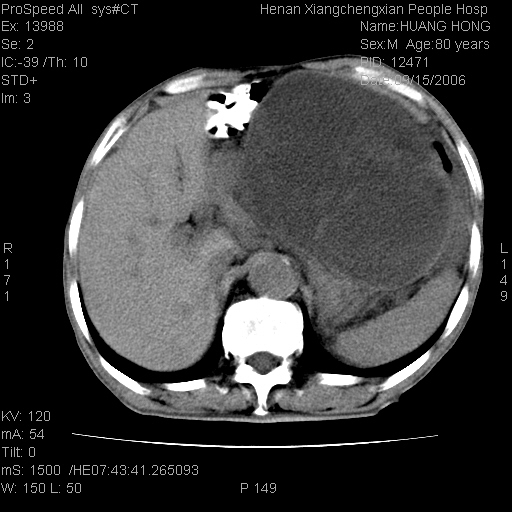

患者, 男, 80岁, 发现上腹部包块1年余,无其它不适.2006-9-14ct片是喝水后扫描2006-9-15ct片没喝水扫描![]() ![]() ![]() ![]() ![]() ![]() ![]() ![]() ![]() ![]() ![]() ![]() ![]() ![]() ![]() ![]() 以上是喝水片 以下是空腹片 ![]() ![]() ![]() ![]() ![]() ![]() ![]() ![]() ![]() ![]() ![]() ![]() ct:胰腺前方、肝脏与胃之间可见巨大类圆形囊性低密度影,大小约152mmx145mmx118mm,上缘平t11椎体上缘,下缘平l3椎体下缘,密度均匀,ct值15hu,其内呈多房分隔,囊壁薄且光滑,边界清晰,周围组织及器官明显受压。肝脏实质内未见异常密度影,胆囊未见异常,胰腺密度未见异常,脾脏大小、形态及密度未见异常,腹膜后间隙未见肿大淋巴结影。 印象:胰腺前方、肝脏与胃之间巨大类圆形囊性低密度影.性质待定。多考虑:.肠系膜巨大囊肿。 守望可可西里发言:支持楼主,考虑肠系膜囊肿,多为小肠系膜。 ysxyy发言:我总觉得这个病人虽然很像肠系膜囊肿,但还是应该强化一下; 下面这几幅图里肿块和主动脉的关系不太清,不知能否除外血管性来源? ![]() ![]() ![]() 病理结果:横结肠系膜间叶瘤.部分区域间质细胞增生活跃. 病理图片 ![]() 良性间叶瘤:是指由两种或两种以上的间叶组织所构成的混合性肿瘤.肿瘤仅发生在腹膜后和肠系膜,.前者较后者多发.良性间叶瘤常发生在肾或四肢,腹膜后较少见,各年龄均可发病.女多与男,预后较好,但术后易复法. 恶性间叶瘤:由两种以上恶性间叶组织成分组成. 光镜:肿瘤由脂肪/血管/平滑肌构成. 原贴地址: http://www.radinet.com.cn/forum_view.asp?forum_id=4&view_id=16217 ok |